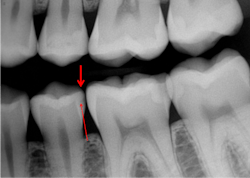

If proximal caries are present, restore them as soon as they are evident on digital radiographs, which represent only 40% or 50% of the actual caries depth. This is usually about one-half to three-quarters through the enamel—not radiographically into dentin as taught in the past (figures 2 and 3).